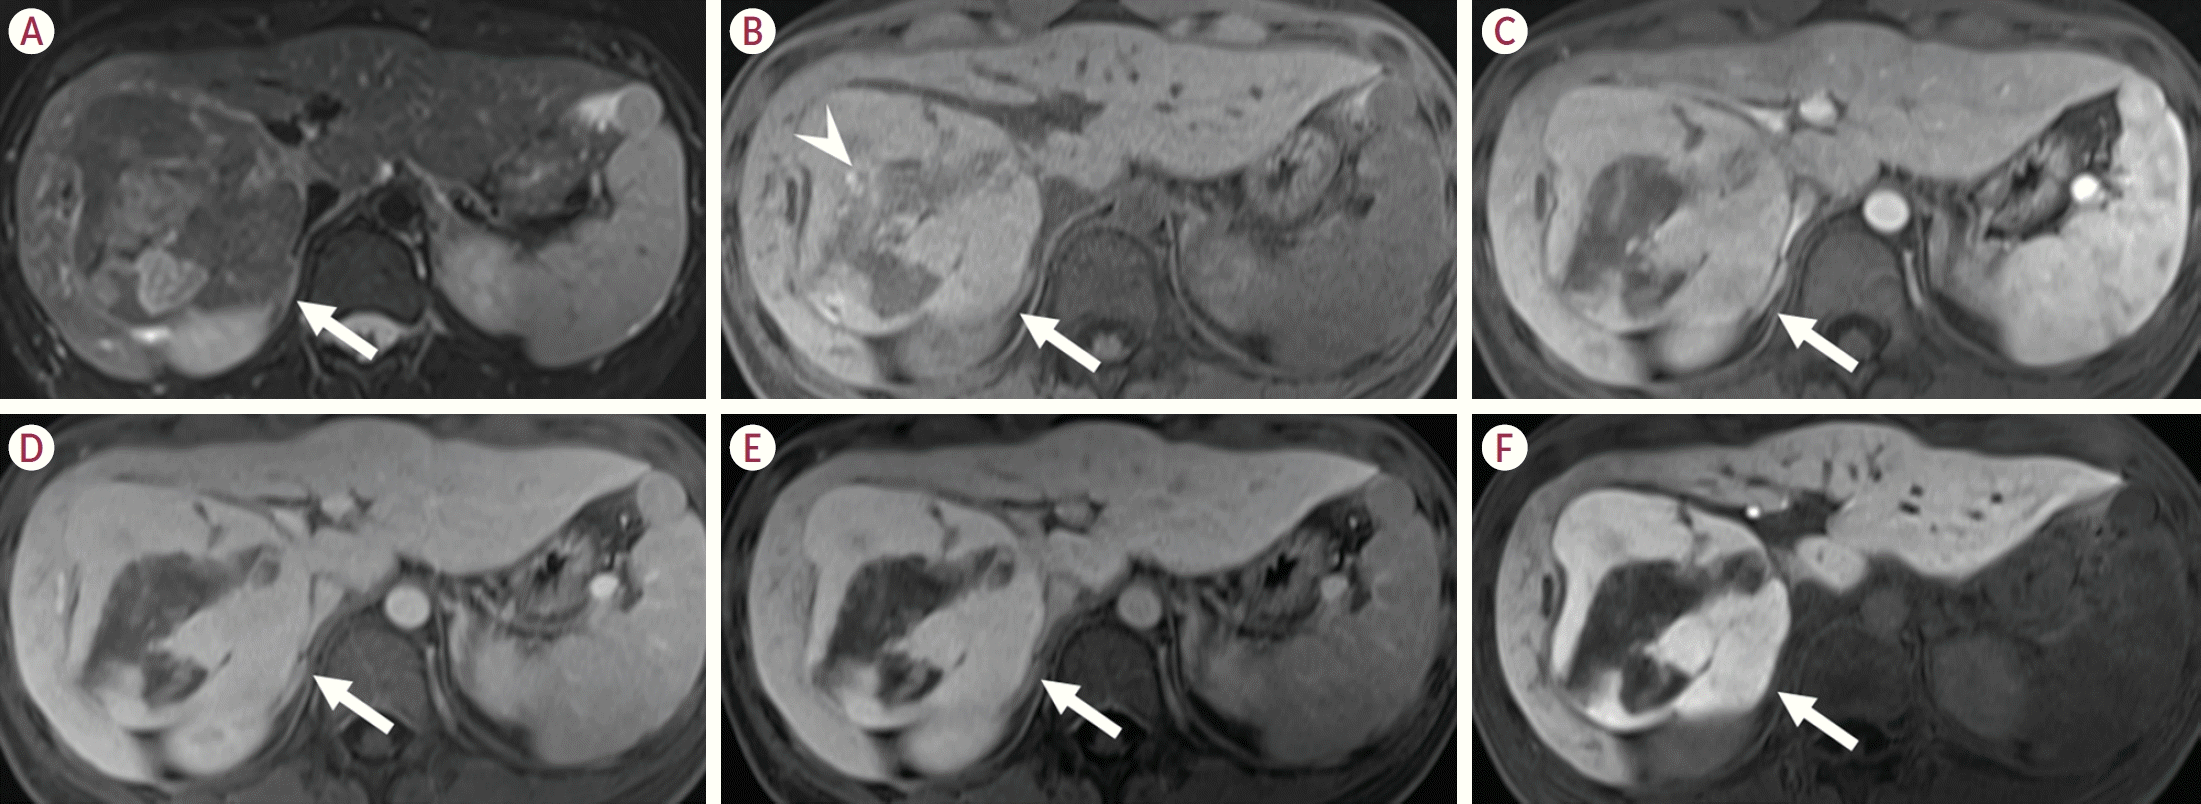

41. Agarwal S, Fuentes-Orrego JM, Arnason T, Misdraji J, Jhaveri KS, Harisinghani M, et al. Inflammatory hepatocellular adenomas can mimic focal nodular hyperplasia on gadoxetic acid-enhanced MRI. AJR Am J Roentgenol. 2014; 203:W408–W414.

42. Evason KJ, Grenert JP, Ferrell LD, Kakar S. Atypical hepatocellular adenoma-like neoplasms with β-catenin activation show cytogenetic alterations similar to well-differentiated hepatocellular carcinomas. Hum Pathol. 2013; 44:750–758.

52. Ducatel A, Trillaud H, Reizine E, Vilgrain V, Sempoux C, Schmidt-Kobbe S, et al. Sonic hedgehog hepatocellular adenoma: magnetic resonance imaging features and correlation with histology. Eur Radiol. 2024; 34:4649–4662.

53. Vernuccio F, Ronot M, Burgio MD, Cauchy F, Choudhury KR, Dokmak S, et al. Long-term evolution of hepatocellular adenomas at MRI follow-up. Radiology. 2020; 295:361–372.

39. Tse JR, Felker ER, Naini BV, Shen L, Shen J, Lu DSK, et al. Hepatocellular adenomas: molecular basis and multimodality imaging update. Radiographics. 2023; 43:e220134.

40. Glockner JF, Lee CU, Mounajjed T. Inflammatory hepatic adenomas: characterization with hepatobiliary MRI contrast agents. Magn Reson Imaging. 2018; 47:103–110.